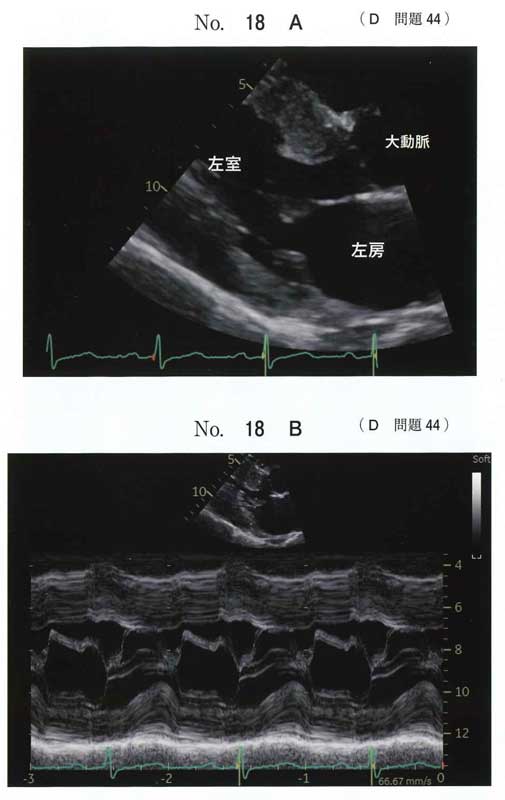

本症例は 閉塞性肥大型心筋症(HOCM)。

エコー所見は心室中隔の肥厚とMモードではSAMですね。

典型的なHOCMの所見です。